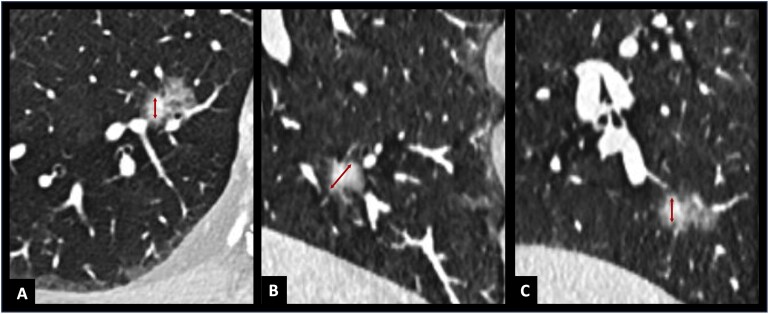

Abstract Image